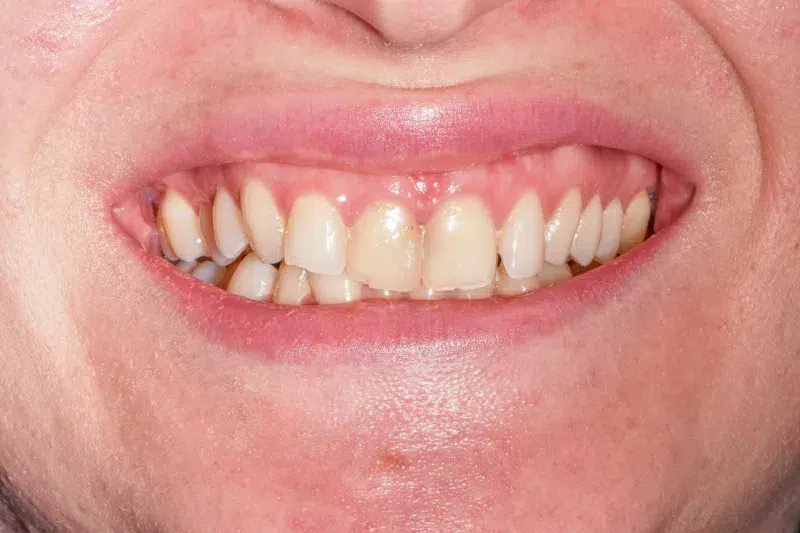

Înainte

Caz de estetică dentară – Fațete ceramică presată E-Max

Provocarea acestui caz a fost în prepararea minim invazivă a dinților centrali rotați și a obține o formă și o culoare cât mai naturală, pacienta dorind un caz de estetică dentară ce să nu fie observabil.

Pacienta a beneficiat de corecție gingivala cu laser pentru uniformizarea asimetriilor gingivale, tratamente endodontice de canal sub microscop, obturațiile vechi (plombe) schimbate cu materiale de compozit cu particule nanoceramice, și fațete dentare din ceramică presată E-Max.

Termen de finalizare 2 săptămâni de la amprentarea finală.